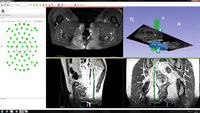

iGyne is an open source software for MR-Guided Interstitial Gynecologic Brachytherapy. It enables on-time processing of the intra-operative MRI data via a DICOM connection to the scanner followed by a multi-stage registration of CAD models of the template and the obturator to the patient images. This allows the virtual placement of interstitial needles during the intervention. Software features include:

• Loading of Applicator CAD models and MR images

• Initial registration of CAD model of the Template to MR images

• Registration Refinement

• Visualization of Registration

• Needle Selection and Display of Virtual Needles relative to Applicator CAD models and Tumor Segmentation